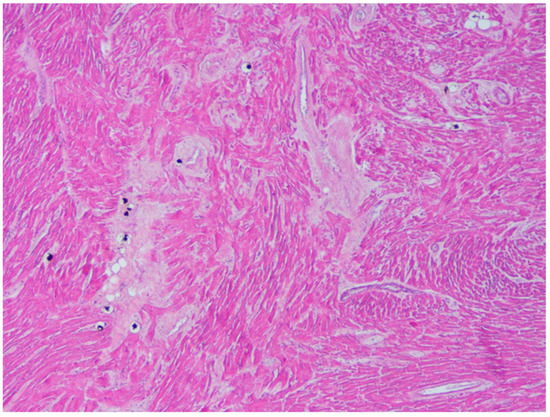

2. Case Report

6.1. Autopsy Findings